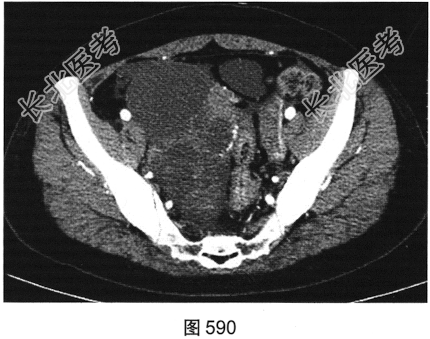

- 多项选择题2.[提示]患者盆腔CT表现见图590、图591。根据以上两幅盆腔CT图像,可以看到哪些阳性表现( )

A、直肠乙状结肠交界区肠管壁厚,强化不均匀

B、双侧髂血管周围多发结节影,可见强化

C、右侧附件区较大囊实性占位性病变,可见不均匀强化

D、右侧附件区多房囊性占位性病变,未见强化

E、盆底腹膜多发结节状软组织影,可见强化

F、盆腔大量积液